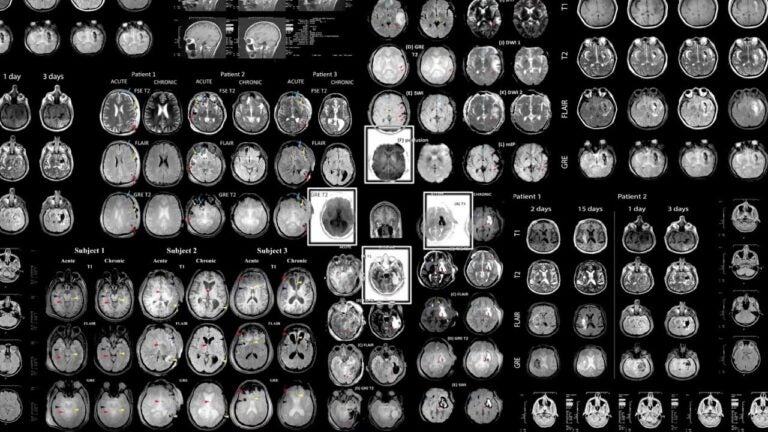

The key to treating and managing many brain diseases is to catch them early, before symptoms even appear. For researchers like Paul Thompson at the USC Mark and Mary Stevens Neuroimaging and Informatics Institute, they believed they could discover hidden factors of diseases using machine learning technology. Calling in the help of USC computer science research assistant professor Greg Ver Steeg, researchers studied how using machine learning to identify potential blood-based markers of Alzheimer’s disease.